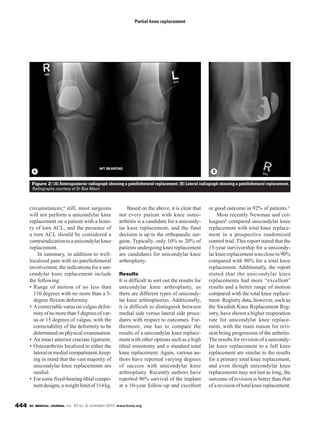

Figure 2: (A) Anteroposterior radiograph showing a patellofemoral replacement. (B) Lateral radiograph showing a patellofemoral replacement.

Radiographs courtesy of Dr Bas Masri.

A B

A patellofemoral replacement

( ) is indicated for the man-

agement of isolated osteoarthritis of

the patellofemoral joint. It has to be

clear that this form of partial knee

replacement is not indicated for pat-

ellofemoral pain in the absence of rad-

iographically proven osteoarthritis.

Figure 2